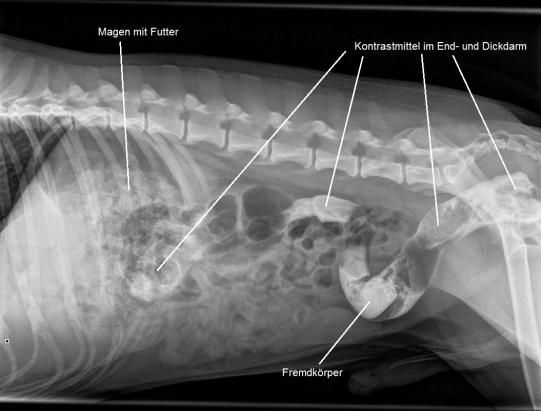

In der Praxis erscheint der Rüde sehr vital und aufgestellt. Beim Abtasten des Bauches ist aber ein harter Knoten zu spüren, welcher den Verdacht nährt, dass sich im Darm des Hundes ein weiterer Stein befindet. Im Röntgen ist denn auch ein dreieckiger, abgerundeter Stein von ca 4x3x2 cm Grösse zu sehen.

Aufgrund des Röntgens ist nicht zweifelsfrei zu klären, ob sich der gefundene Stein im Dünn- oder Dickdarm befindet. Sollte sich der Fremdkörper im Dünndarm aufhalten, muss davon ausgegangen werden, dass er das Darmrohr blockiert und damit eine Operation notwendig ist. Falls sich der Kiesel aber trotz seiner beträchtlichen Grösse schon durch den Dünndarm gezwängt hat und im Dickdarm liegt, kann davon ausgegangen werden, dass er ohne Chirurgie durch den Hund ausgeschieden werden kann.

Ein Ultraschall nährt die Hoffnung, dass letztere Möglichkeit zutrifft. Zur zweifelsfreien Bestätigung wird ein sogenanntes Kontrast-Enema durchgeführt: Hierbei wir durch einen dünnen Katheter ein flüssiges Kontrastmittel in den Enddarm des Hundes eingebracht, welches dann beweist, dass der Stein eindeutig im Dickdarm liegt. Tierarzt und Tierheimpersonal können aufatmen, eine Chirurgie ist nicht notwendig.